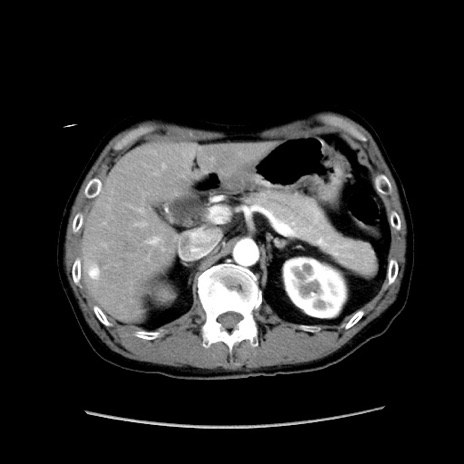

症例37(横断像)

【症例】40歳代 男性

【主訴】腹痛

【現病歴】4時間ほど前に電車に乗車中に臍部上より腹痛出現。徐々に増悪し起立困難となり、救急外来受診。生ものは数日食べていない。今朝お雑煮を食べた。

【身体所見】BT 36.8℃、BP 117/84mmHg、HR 91/min、SpO2 97%、苦悶様、腹部:臍上部広範囲圧痛あり、反跳痛±

【データ】WBC 8100、CRP 0.03